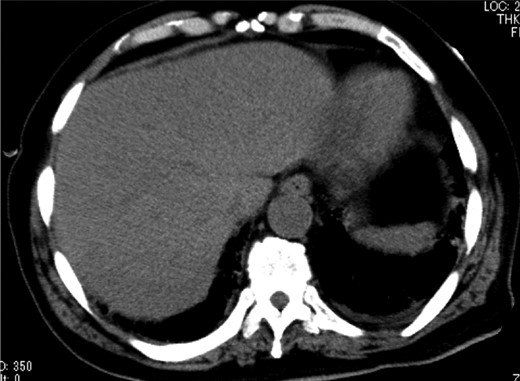

A 79-year-old man with acute abdominal pain had gone to a nearby hospital. As HPVG was detected by abdominal computed tomography (CT), he was transferred to our hospital for further examination and treatment. He had no remarkable past medical history. When he arrived at our hospital, his vital signs were relatively stable (body temperature: 37.2°C; blood pressure: 112/74 mmHg; pulse rate: 68 beats/min). However, physical examination revealed abdominal distention, rebound tenderness and abdominal guarding as signs of peritoneal irritation. The laboratory findings indicated acute inflammation (white blood cell count of 18 400/μL and Creactive protein concentration of 17.7 mg/dL), dehydration and metabolic acidosis (a level of base excess of −7.0 mmol/L). Creatine kinase was remarkably elevated (28 327 IU/L) (Table 1). Plain abdominal radiographs showed distention of the small intestine and suggested subileus (Fig. 1). Contrast-enhanced abdominal CT revealed HPVG (Fig. 2a), a contrast defect in a region of the small intestine, and a small amount of ascites around the intestine. There was no thrombus in any artery; however, the wall of the appendix was moderately thickened when we reevaluated the images retrospectively (Fig. 2b). We performed an urgent laparotomy with the diagnosis of generalized peritonitis caused by intestinal necrosis. A small amount of turbid ascites and a dilated small intestine were observed in the peritoneal cavity. Although the entirety of the small intestine and colon were explored, no intestinal ischemia was detected. Then, we found discoloration of the appendix with wall thickening. We thus made a clinical diagnosis of peritonitis caused by gangrenous appendicitis. Although the appendix wall was fragile, no macroscopic perforation of it was observed. We performed appendectomy and abdominal drainage. Based on the pathological findings, the patient was diagnosed with gangrenous appendicitis, with no evidence of malignancy (Fig. 3). Escherichia coli was positive in the ascitic culture. After the surgery, intravenous antibiotic treatment (meropenem) was administered. The patient subsequently went into septic shock with disseminated intravascular coagulation (DIC). He was therefore admitted to the intensive care unit (ICU), where he received blood purification therapy. The CT images on Day 7 after the surgery showed that HPVG had disappeared (Fig. 4). He left the ICU 7 days after the surgery and was discharged from the hospital another 10 days later.

Contrast-enhanced abdominal CT revealed HPVG (a, black arrow) and thickening of the appendix (b, white arrow).